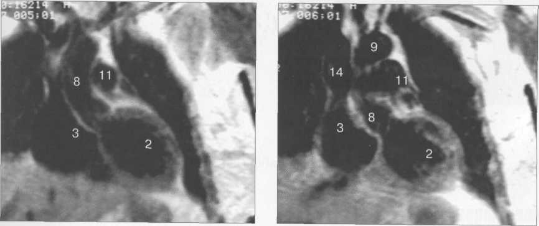

Рис. 9.47. МРТ сердца. Аксиальная плоскость.

Здесь и на рис. 9.48—9.52:

I — правый желудочек, 2 — левый желудочек, 3 — правое предсердие, 4 — левое предсердие, 5 — межжелудочковая перегородка, 6 — межпредсердная перегородка, 7 — задняя стенка левого желудочка, 8 — восходящая часть аорты, 9 — дуга аорты, 10 — нисходящая часть аорты, 11 — легочный ствол, 12 — правая легочная артерия. 13 — левая легочная артерия, 14 — верхняя полая вена, 15 — нижняя полая вена, 16 — трахея.

Рис. 9.50. МРТ сердца. Фронтальные сечения.

Рис. 9.51. МРТ сердца. Сечения по короткой оси левого желудочка.

Рис. 9.52. МРТ сердца. Четырехкамерные сечения.

На рис. 9.47—9.52 представлены Т1-ВИ наиболее часто используемых МР-сечений сердца.